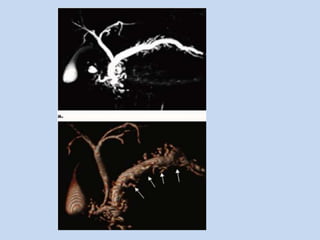

• In post surgical complications:

- The utility of MRCP has been demonstrated in the

evaluation of the surgically altered pancreatobiliary

tract.

- These alterations include

1) biliary – enteric anastomoses

2) pancreaticoenteric anastomoses

3) duct-to-duct anastomoses

• MRCP demonstrates the anastomoses & also the

complications such as – strictures, intraductal stone

formation, & anastomotic leak.

• In pancreatic divisum :

- occurs in 5.5 – 7.5% individuals

- MC variant of pancreatic duct, where the dorsal &

ventral anlage of the pancreas fail to fuse – resulting

in two separate drainage routes for pancreatic

secretions.